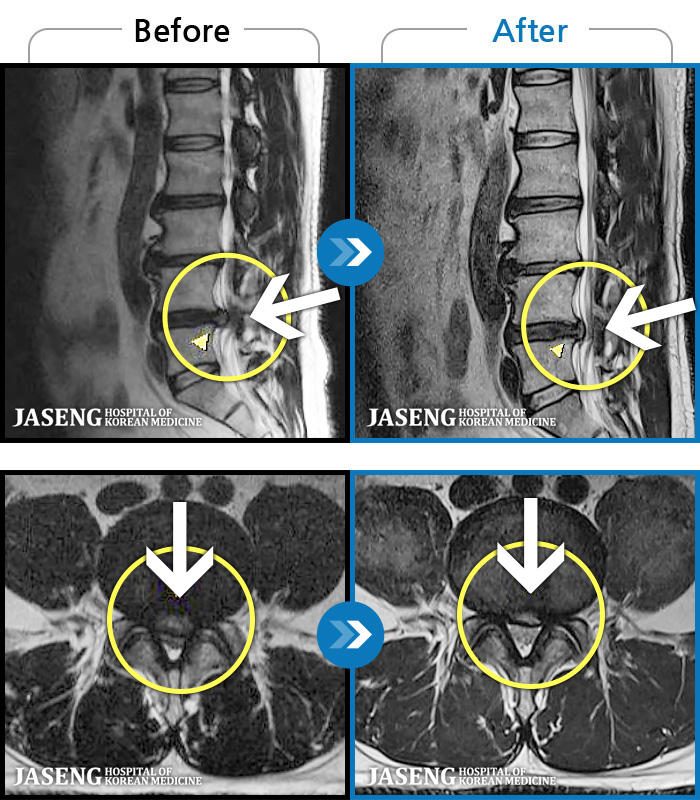

97 MRI ũ ʸ Ȯϼ.